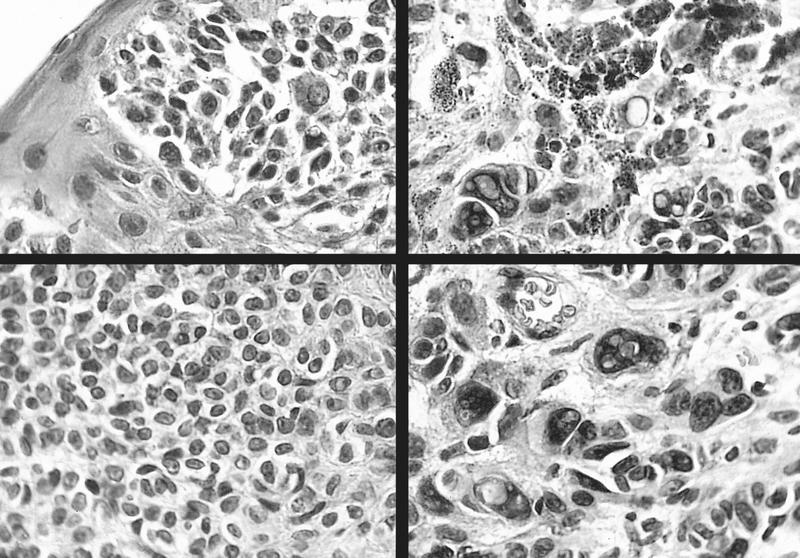

- Nevomelanocytes organized into intraepithelial nests of oval cells (type A), sheets of oval to cuboidal cells (type B), and spindled cells in subepithelium (type C)

- Often (50%) with solid and prominent cystic inclusions of conjunctival epithelium and chronic inflammatory infiltrate

- May have atypical features and mitotic figures during growth periods

- Compound (70 - 78%):

- Most common, nevi cells in epithelium and subepithelial connective tissue

- Cells have cysts lined by cuboidal and goblet cells and intranuclear inclusions

- May have large pigmented cells with prominent basophilic nucleoli

- Usually mixed inflammatory cells

Cystic compound nevus: